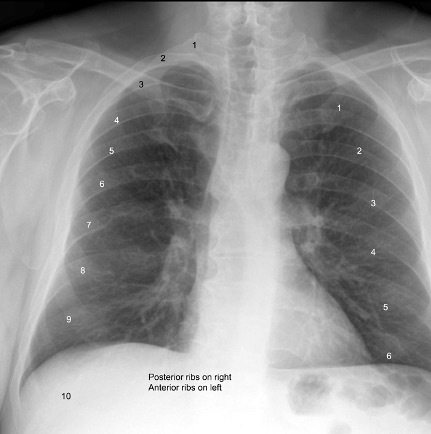

When standing, most adults can take an inspiration that brings the domes of the hemidiaphragm to which rib number?

A

• Rib 10

Q

When seated, most adults can take an inspiration that brings the domes of the hemidiaphragm to which rib number?

• Anywhere from Rib 8 to Rib 10

If the lungs are hypoinflated, the radiography will show the diaphragm at which rib?

• Rib 7